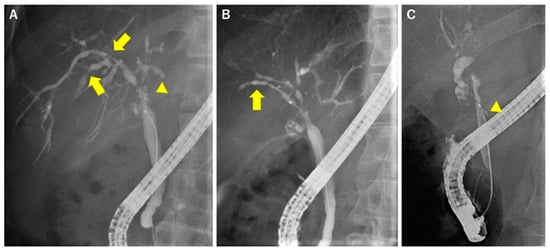

2. Radiological Images of PSC

4. POCS for Diagnosing PSC